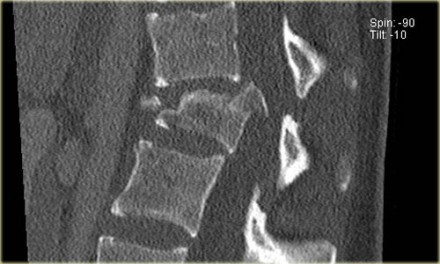

The findings are:

- Morphology: Burst - 2 points

- PLC: very subtle widening of right facet joint - 2 or 3 points

- TLICS based on imaging: 4 or 5 points

A spondylodesis was performed.